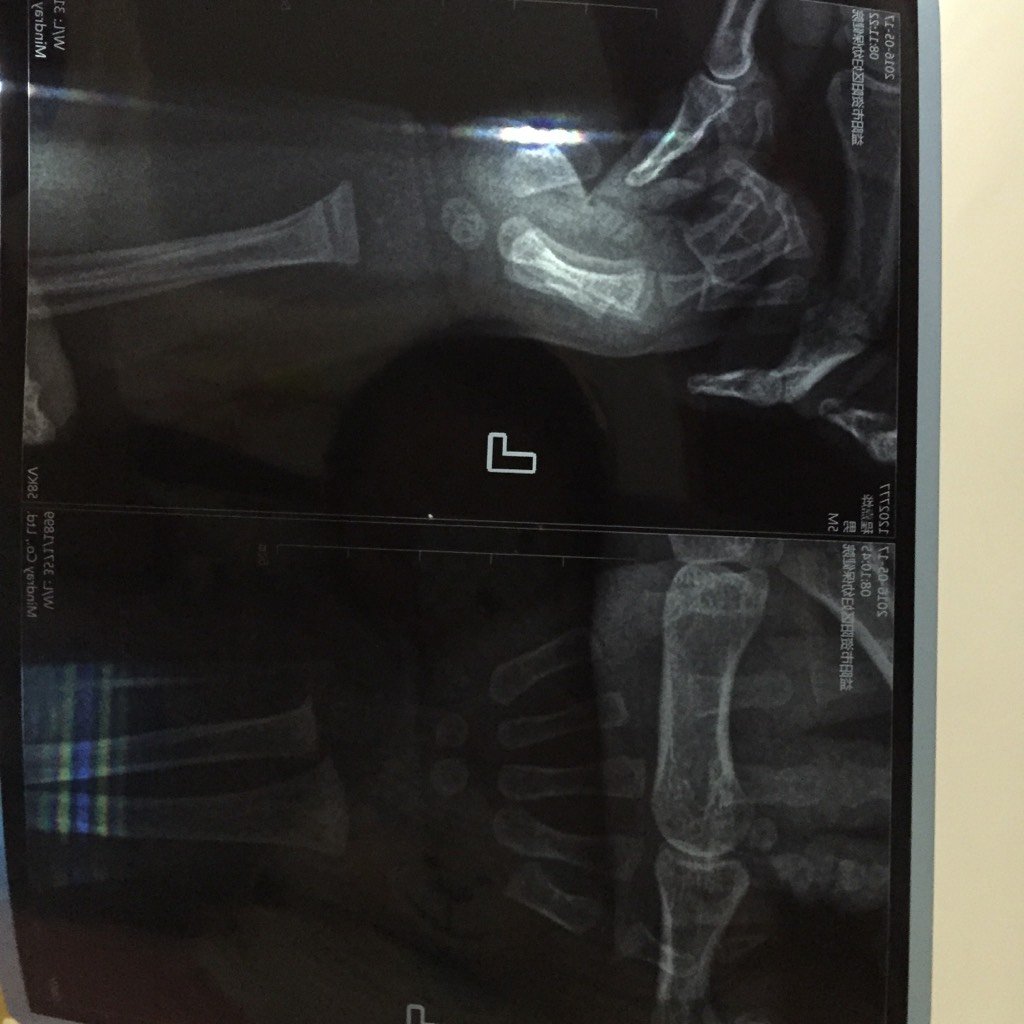

之前去医院检查,医生说有点轻度肋骨外翻,后来复查发现严重了,补查了一个腕关节侧位,检查所见:左桡尺骨干骺端增宽,呈毛刷状改变,骨骺软骨盘增宽,临时钙化带消失,意见是佝偻病,医生让一天1粒鱼肝油,4粒维生素D.据说不多了会中毒,请大家给点意见,量会不会太大了